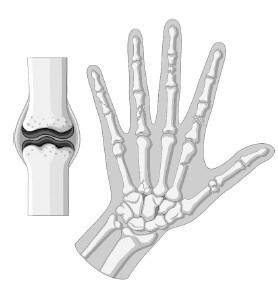

Здоровые рука и суставы. ![]() Рука с артритными суставами. Кроме того, старение приводит к дефициту проприоцептивных навыков – ощущения положения тела и ориентации в пространстве. Он возникает при снижении количества тензорецепторов в связках, из-за чего нарушается восприятие расположения суставов в пространстве. ![]() Старение суставного хряща приводит к воспалению и аномальному росту. Стареющие мышцы Саркопения – это термин, под которым подразумевают снижение массы скелетных мышц и их возможностей нормального функционирования. Этот прогрессирующий возрастной синдром сопряжен и с другими недостатками: снижением качества жизни и повышенным риском инвалидности и смерти. К потере мышечной массы приводит истончение миофибрилл внутри мышечных волокон, из-за чего снижается толщина самого волокна (чаще встречается у волокон 2-го, быстро сокращающегося типа). Миофибриллы атрофируются со скоростью от 3 % до 8 % в каждые 10 лет (в возрасте от 30 лет). А для людей старше 65 лет этот показатель еще больше возрастает. Потеря мышечной массы может быть связана c уменьшением количества самих волокон. В возрасте от 24 до 50 лет скорость атрофии мышечных волокон увеличивается с 5 % до 35 %. Считается, что возрастные изменения в нервно-мышечном соединении приводят к тому, что связанный с ним нейрон отделяется от мышечного волокна (лишается иннервации), а затем умирает в результате апоптоза (см. параграф «Запрограммированная гибель клетки: апоптоз» на стр. 51). ![]() На этих МРТ-снимках изображены бедра здорового 31-летнего мужчины (вверху) и здорового 81-летнего мужчины (внизу). Потеря мышечной массы и увеличение фиброзно-жировой ткани – характерные признаки саркопении. Процесс старения не щадит и сателлитные клетки, которые в норме отвечают за восстановление поврежденных мышц. С возрастом их популяция сокращается на целых 50 %. ![]() Считается, что танцы – это увлекательный способ замедлить или обратить вспять процесс потери скелетных мышц. Кроме того, у пожилых людей танцы улучшают здоровье мозга. На работоспособность мышц влияет и тип разрушенных мышечных волокон. Оказывается, что старение приводит к потере двигательных нейронов, которые иннервируют 2-й тип мышечных волокон, быстро сокращающихся. Такое изменение не только уменьшает количество волокон, но и способствует тому, что некоторые волокна начинает иннервировать 2-й, медленно сокращающийся тип двигательных нейронов. Это, в свою очередь, изменяет скорость реакции, удельную мощность мышц, их координацию и силу. Мышечная архитектура страдает и из-за разрастания фиброзно-жировой ткани. Все это накладывается на сопутствующие возрастные изменения и влияет на динамику мышечно-костных отношений. В результате снижается действенность упражнений, направленных на увеличение мышечной силы и костной массы. Многие исследователи говорят, что скорость потери мышечной массы можно компенсировать регулярными упражнениями (особенно танцами), поэтому пословица «движение – жизнь» глаголет истину. |